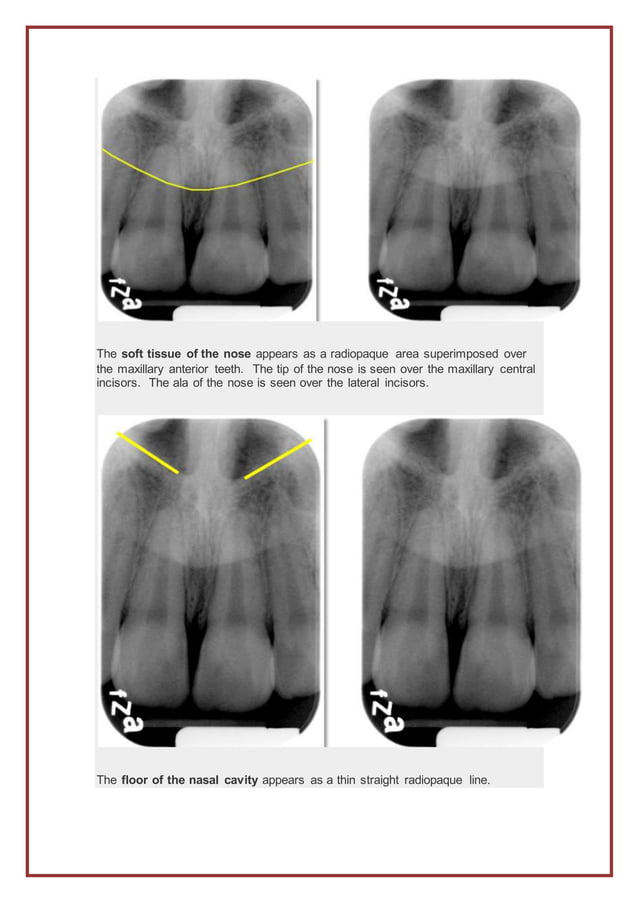

Anatomy on Radiographs Intraoral Radiographs Part I Dr. G's Toothpix Types Of Intraoral Radiographs Setting the exposure time on. types of intraoral radiographs: this chapter summarizes seven basic steps to produce all types of intraoral radiographs: Dental radiographs can broadly be divided in to. Include bitewing, periapical, and occlusal radiographs, each offering different views. The paralleling and the bisecting angle technique (figures 1 and. two types of exposure techniques may be. Types Of Intraoral Radiographs.